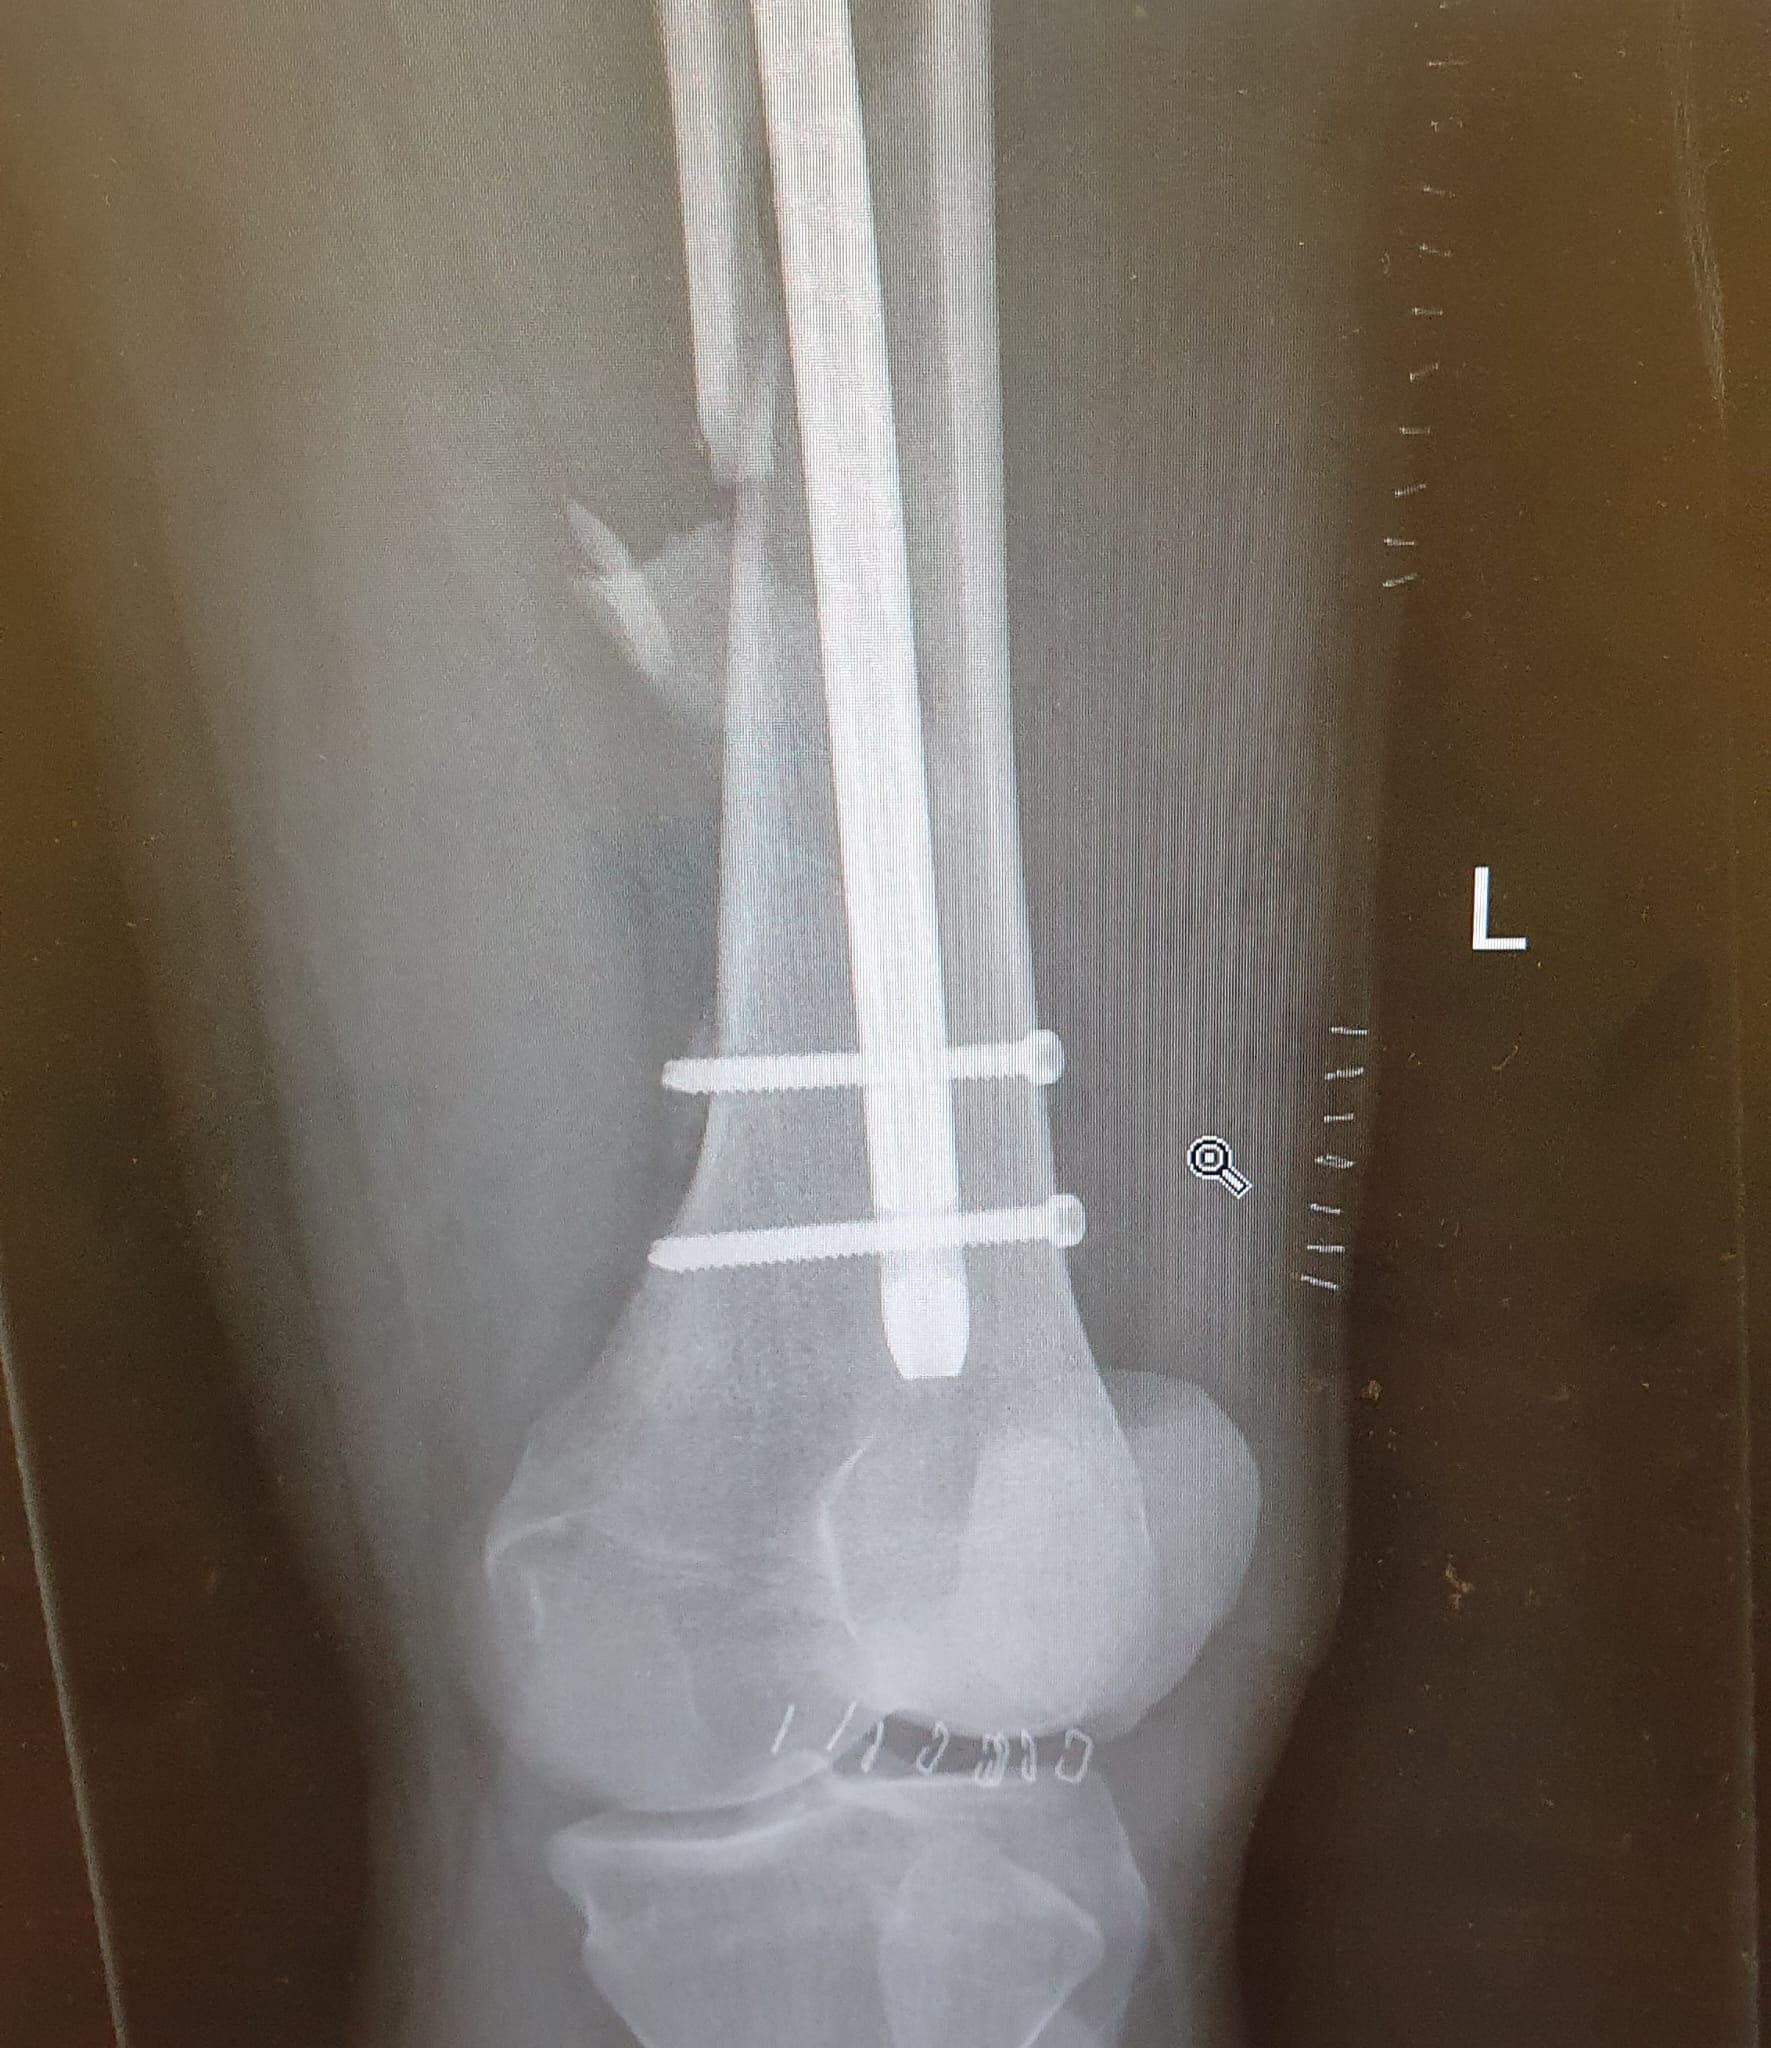

This can happen with femoral nails even under normal weight bearing and if the operating surgeon had just put a distal locking screw in the dynamic hole (the oblong hole just under the circular hole which the screw has broken in, known as the static hole) then this wouldn't be an issue as the nail would dynamise and compress the fracture site and would actually lead to continued callus formation and healing. But since they didn't do that simple thing they now need to go back in and put another screw in. Waste of time and increases risk of infection. The reduction of the fracture is great though and there is callus formation so it is healing, I don't know why they didn't bother putting that 2nd screw in.

t. orthopaedic surgeon (I can't find an XR which doesn't have a knee replacement in it but the principle is the same).

Based. Here's one I did a few years with a mate of mine when we were juniors, this was a lot more fucked and the patient never came back for follow up so I don't know what happend to them for sure, hopefully they ar fine.

The rest of the nail (can't be arsed to post lateral XRs, nothing that exciting about them and this new captcha is fucking gay).